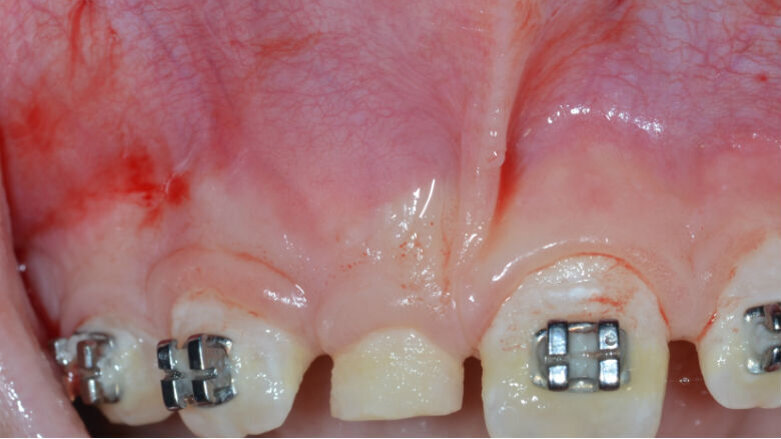

Il paziente (maschio, di anni 10) si presenta alla nostra attenzione lamentando la mancata eruzione in arcata dell’elemento 1.1 associata a una tumefazione con consistenza solida, non dolente e non dolorabile situata in corrispondenza dell’apice dell’elemento 5.1 (Fig. 1).

In seguito all’esame obiettivo e dopo aver preso visione dello studio radiografico del caso (effettuato mediante esami di 1° e 2° livello) si diagnostica la presenza di una neoformazione di dimensioni approssimativamente pari a 7,4 x 8,3 mm posizionata tra gli elementi 5.1 e 5.2 il cui aspetto è compatibile con quello di un odontoma (Figg. 2, 3). La presenza di questa neoformazione impedisce il normale tragitto eruttivo dell’elemento 1.1 che appare inoltre leggermente mesio-inclinato: questa condizione indica come terapia elettiva l’enucleazione chirurgica della massa neoformata e la contestuale cementazione di un attacco ortodontico per procedere al recupero dell’elemento ritenuto.